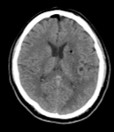

脳出血における神経内視鏡手術前後の画像